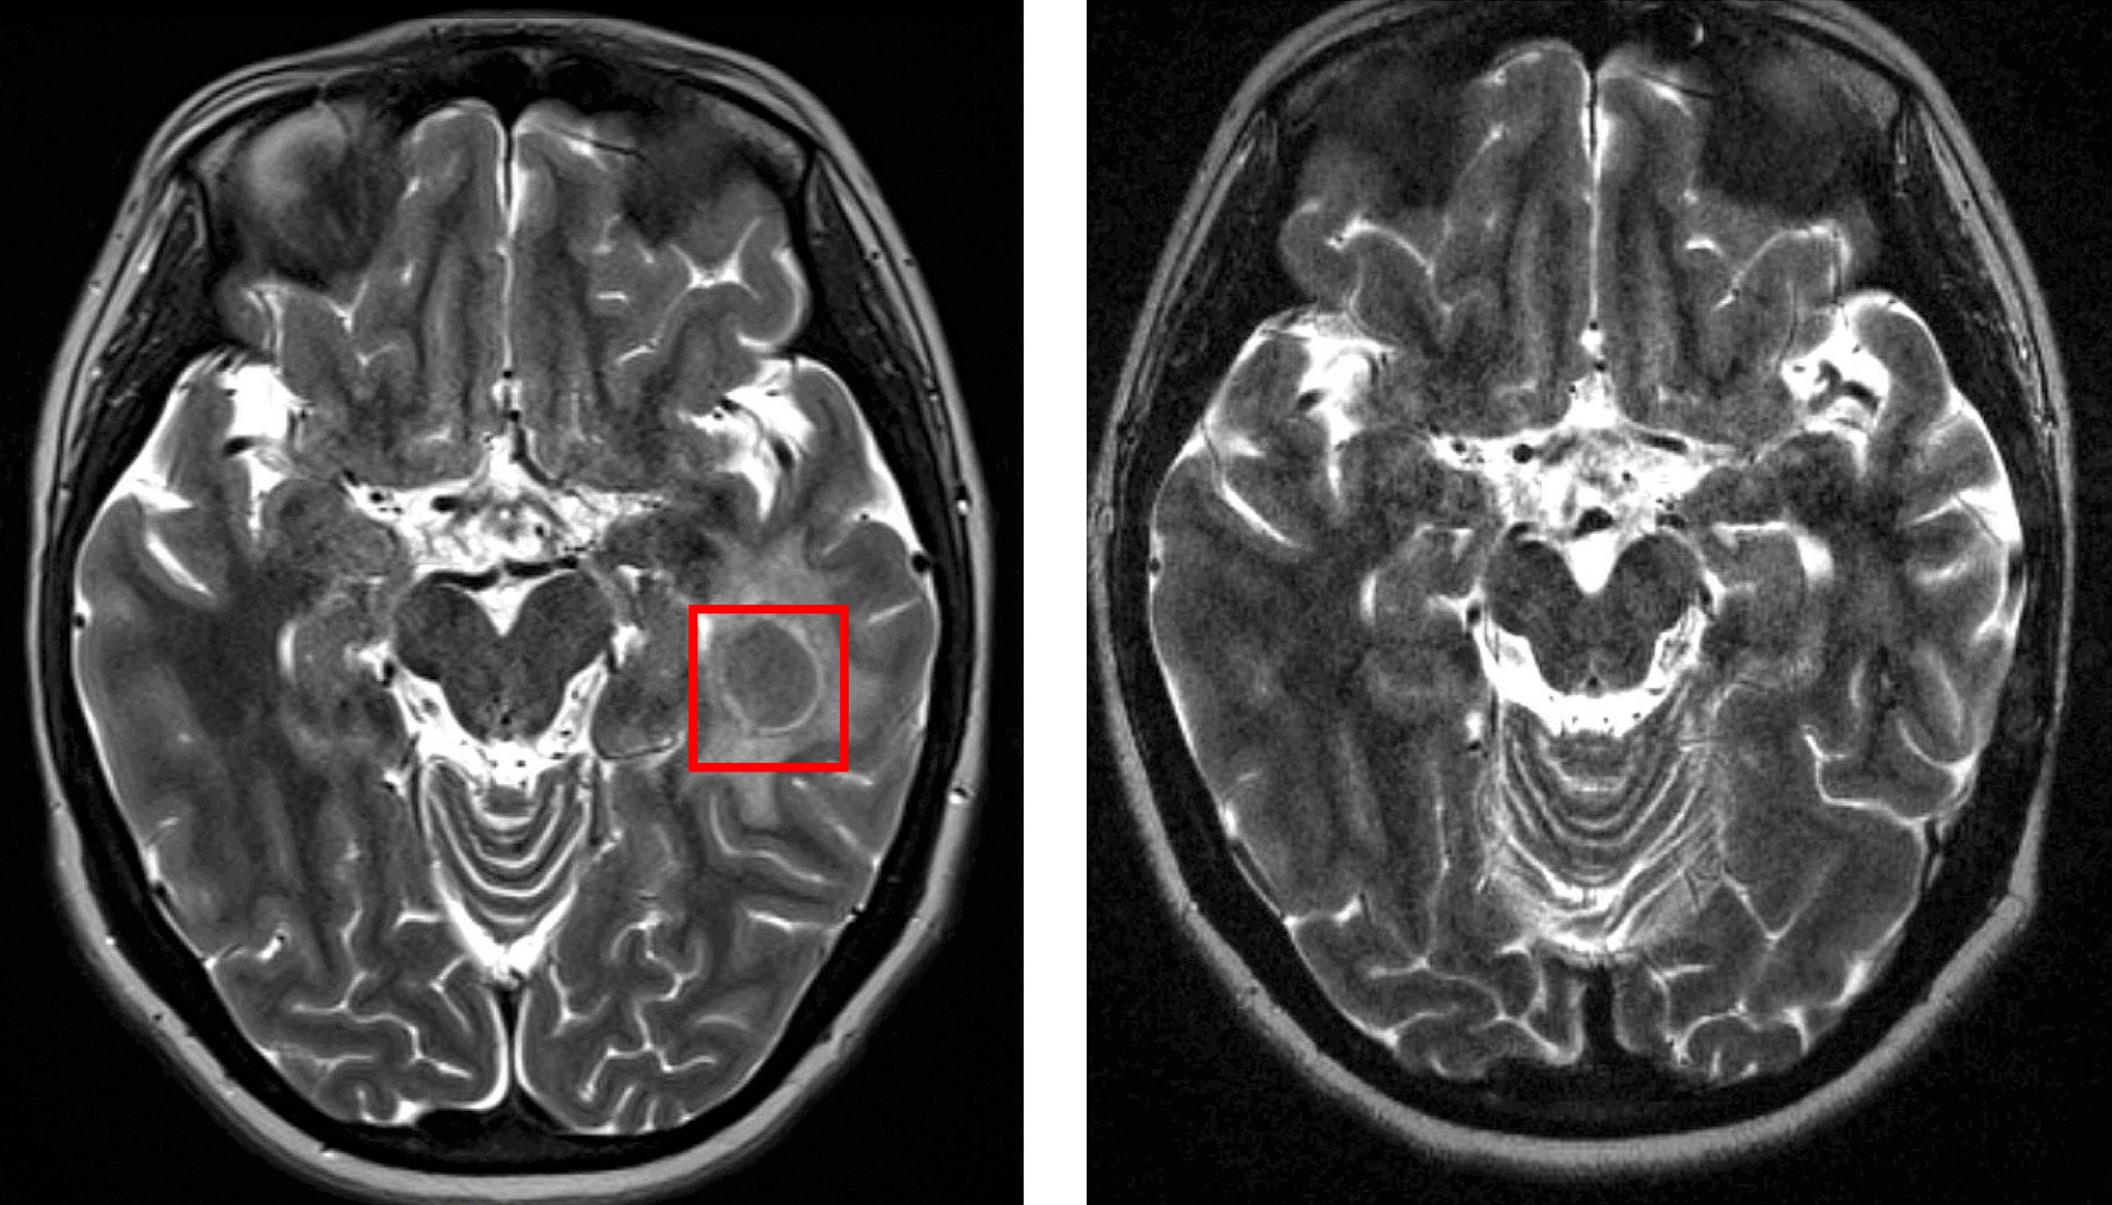

Figure 1. COVID-19 may be particularly hazardous to people with sickle cell disease and pregnancy because of associated changes to the immune system, multiple thrombosis risks and compromised pulmonary function. Given the risks, potential modifying interventions warrant consideration.